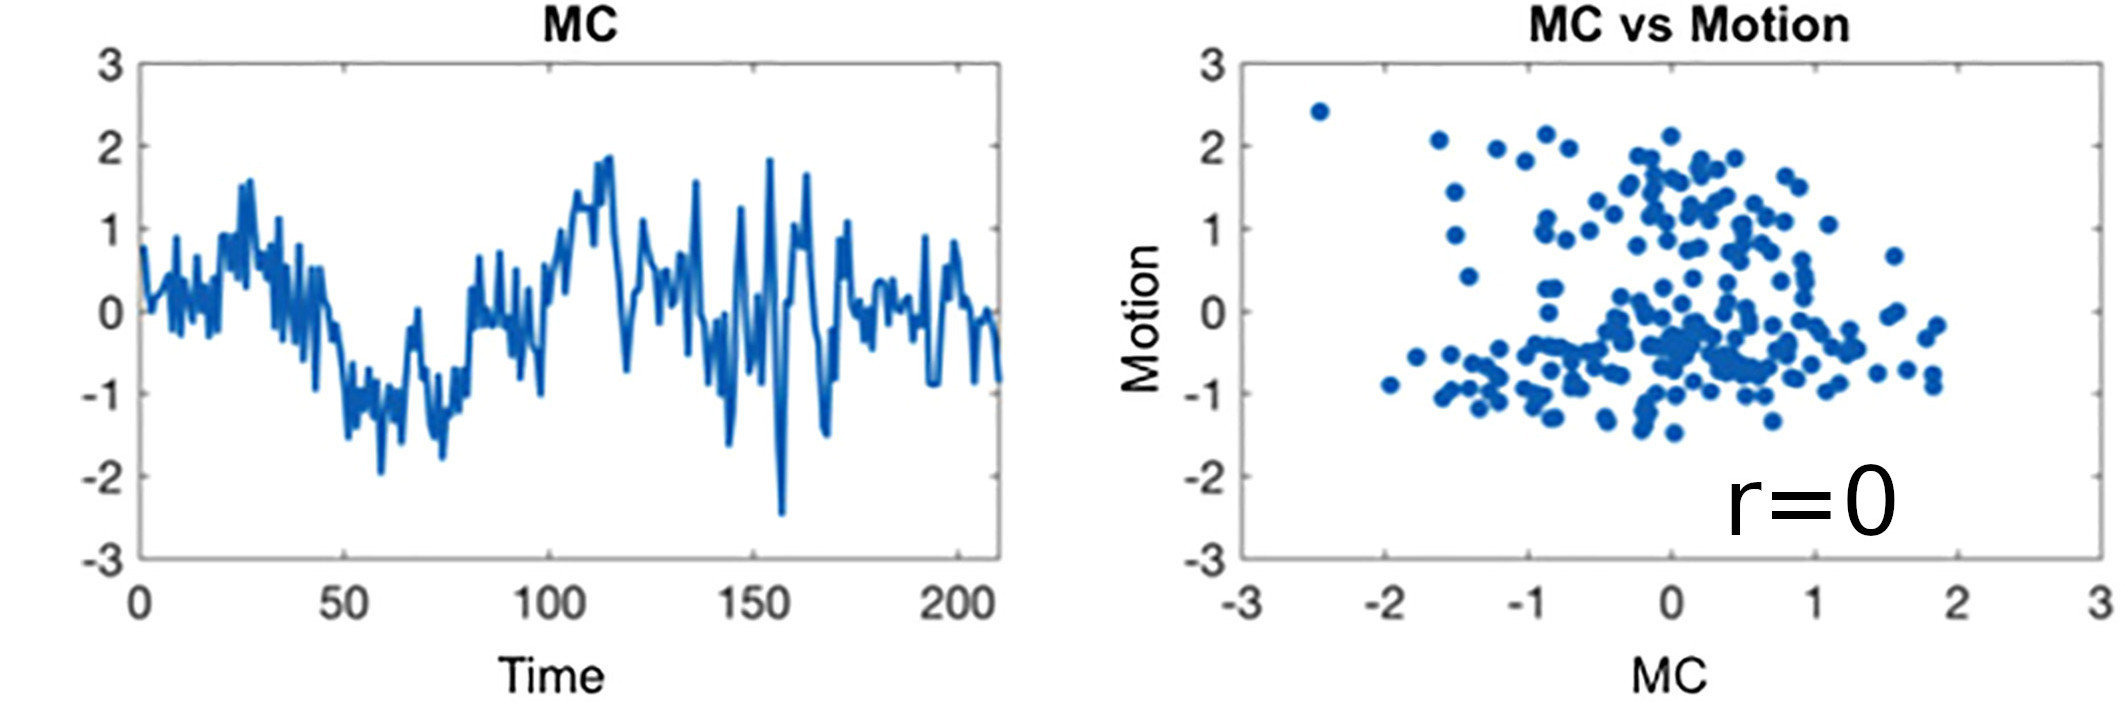

Sequential vs Simultaneous denoising

Performing denoising in sequential steps, rather than in parallel, might reintroduce removed artefacts

Lindquist et al. 2019 (Hum. Brain Mapp.)

Methods: CVR and lag maps

CVR and lag maps: L-GLM with each lagged regressor and nuisance regressors (12 motion parameters and low frequency trends), voxelwise selection of the lagged model with highest explained variance (R²), normalisation to MNI152 template (2.5 mm isotropic)

We compared four pipelines:

- L-GLM with motion parameters (see above, SimMot): $$ Y = P_{ET}CO_2{hrf}_{vx} + Mot + Poly + n $$

- Non-optimised CVR map (measurement delay only, Non Opt): $$ Y = P_{ET}CO_2{hrf}_{bulk} +n $$

- L-GLM without motion parameters (NoMot): $$ Y = P_{ET}CO_2{hrf}_{vx} + n $$

- L-GLM without motion parameters, motion regressed out before (SeqMot): $$ [Y \perp (Mot,Poly)] = P_{ET}CO_2{hrf}_{vx} + n $$

We compared four pipelines:

- L-GLM with motion parameters (see above, SimMot): $$ Y = P_{ET}CO_2{hrf}_{vx} + Mot + Poly + n $$

- Non-optimised CVR map (measurement delay only, Non Opt): $$ Y = P_{ET}CO_2{hrf}_{bulk} +n $$

- L-GLM without motion parameters (NoMot): $$ Y = P_{ET}CO_2{hrf}_{vx} + n $$

- L-GLM without motion parameters, motion regressed out before (SeqMot): $$ [Y \perp (Mot,Poly)] = P_{ET}CO_2{hrf}_{vx} + n $$

To improve CVR estimates, compute lagged-regression of signal of interest and noise simultaneously.

Take home message #2